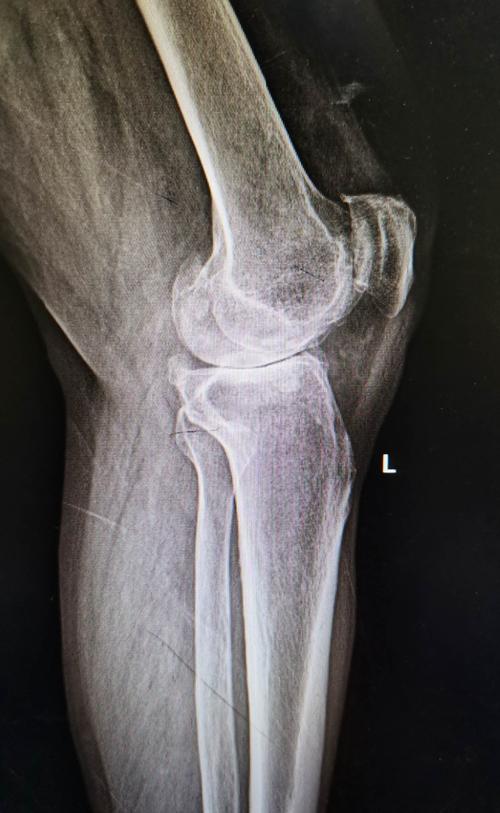

左膝关节活动度约10—130度,右膝关节活动度约15—130度,行走50

术后三个月膝关节主动屈曲活动度130度,被动138度,伸膝活动度正常.

我院第一例人工膝关节置换术后病人术后4个月余复查.